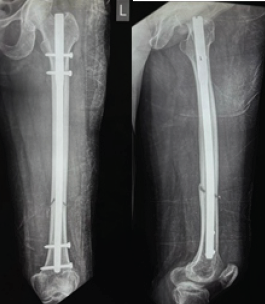

Figure 2: Anteroposterior and lateral views at 1.5 months showing distal third fracture of the femur with retrograde nail.

Out of all study participants, 58 patients had closed fractures and rest 2 patients had compound fractures. The mean operation-injury interval was 5.5 ± 0.67 days for antegrade nailing and 5.8 ± 0.65 days for retrograde nailing. The mean duration of the surgery was 85 ± 2.15 min for retrograde nailing and 95 ± 1.39 min for antegrade nailing. Mean time for radiological union with retrograde nailing was 10 ± 0.38 weeks (Fig. 1, 2, 3, 4) and with antegrade nailing, it was 14 0.44 weeks (Fig. 5, 6).

Figure 3: Anteroposterior and lateral views at 3 months showing distal third fracture of femur with retrograde nail.